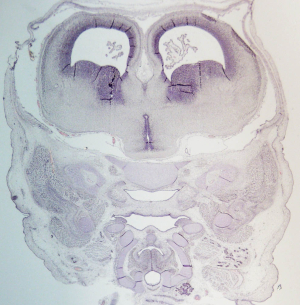

Stage 21

CfS 21

d37-39